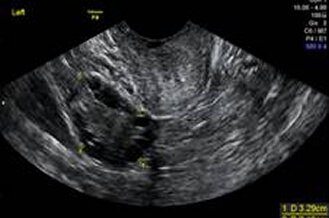

Normal ovaries